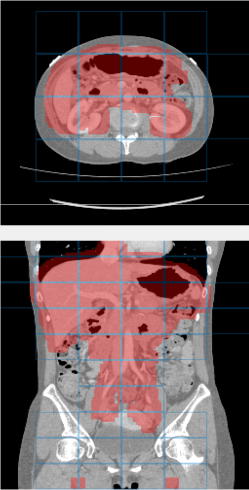

Training and validation: Our dataset includes 331 contrast-enhanced abdominal clinical CT images in the portal venous phase used for pre-operative planning in gastric surgery. Each CT volume consists of slices of pixels. The voxel dimensions are [0.59-0.98, 0.59-0.98, 0.5-1.0] mm. A random split of 281/50 patients is used for training and validating the network, i.e., determining when to stop training to avoid overfitting. In both training stages, we employ smooth B-spline deformations to both the image and label data, as proposed by Çiçek et al. (2016). The deformation fields are randomly sampled from a normal distribution with a standard derivation of 4 and a grid spacing of 32 voxels. Furthermore, we applied random rotations between and to the training images for plausible deformations during training. No deformations were applied during the testing. We trained 200,000 iterations in the first stage and 115,000 in the second. Table 1 summarizes the Dice similarity scores for each organ labeled in the 50 validation cases. On average, we achieved a 7.5% improvement in Dice scores per organ. Small, thin organs such as arteries especially benefit from our two-stage hierarchical approach. For example, the mean Dice score for arteries improved from 59.0 to 79.6% and from 54.8 to 63.1% for the pancreas. The effect is less pronounced for large organs, like the liver, the spleen, and the stomach. Fig. 3 shows an example result from the validation set and illustrates the tiling approach. The 3D U-Net separates the foreground organs well from the background tissue of the images.

Testing: Our test set is different from our training and validation data. It originates from a different hospital, scanner, and research study with gastric cancer patients. 150 abdominal CT scans were acquired in the portal venous phase. Each CT volume consists of slices of pixels. Voxel dimensions are [0.55-0.82, 0.55-0.82, 0.4-0.80] mm. The pancreas, liver, and spleen were semi-automatically delineated by three trained researchers and confirmed by a clinician. Figure 4 shows surface renderings for comparison of the different stages of the algorithm. A typical testing case in the first and second stages is shown using non-overlapping and overlapping tiles (Eq. 4). Dice similarity scores are listed in Table 2. This dataset provides slightly higher image quality than our training/validation dataset. Furthermore, its field of view is slightly more constrained to the upper abdomen. This probably explains the better performance for liver and pancreas compared to the validation set in Table 1.